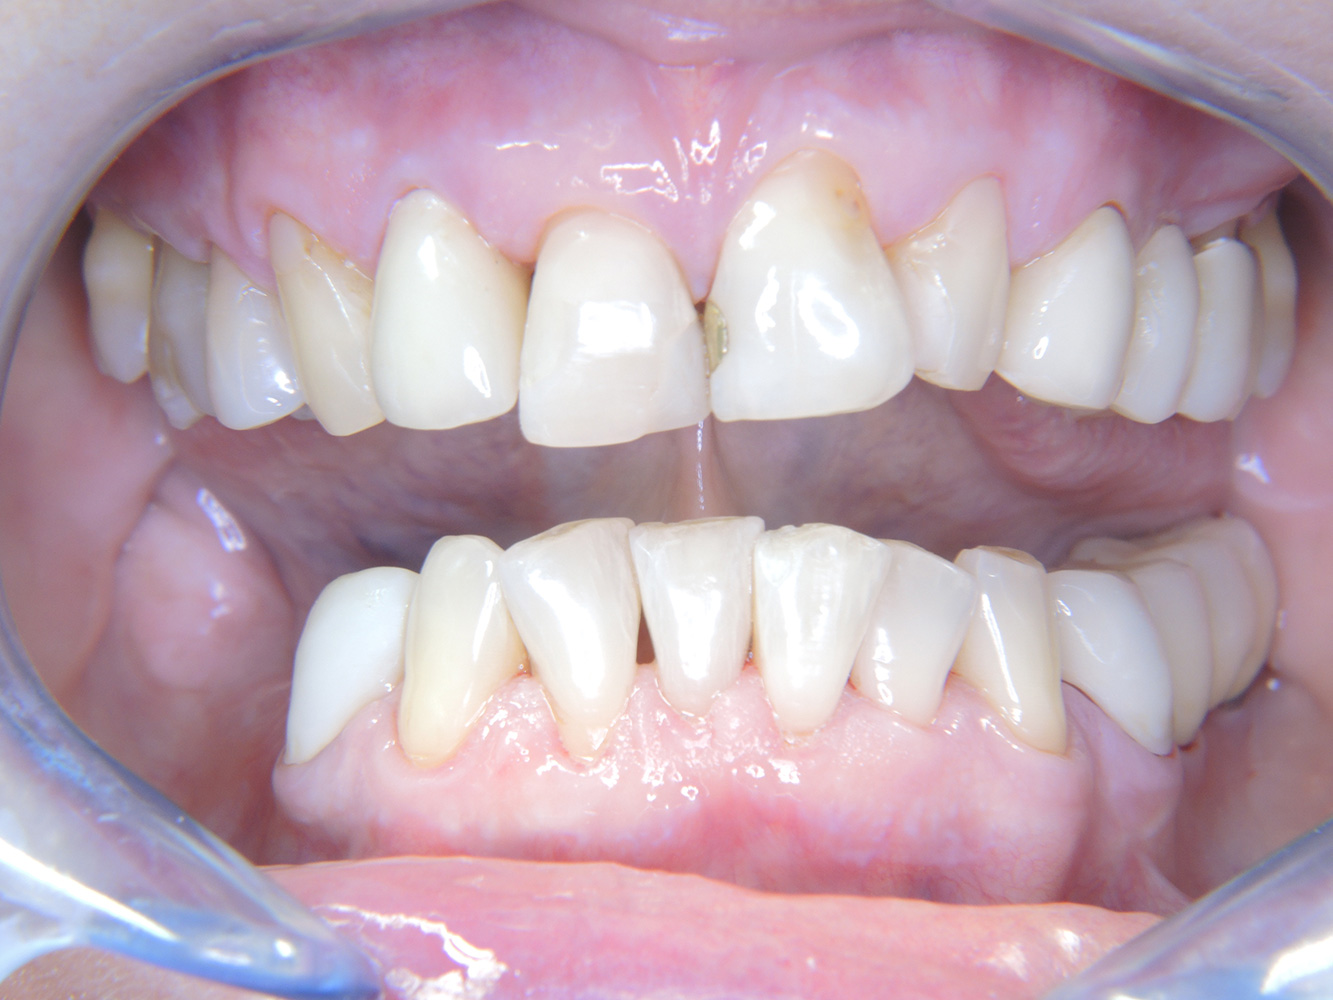

Paciente sana con enfermedad periodontal previa*

La paciente de 68 años no tiene enfermedades previas relevantes de la salud general ni toma medicación; sus hábitos alimentarios tampoco suponen un riesgo especial. La paciente tiene dos implantes (tercer cuadrante, desde hace cinco años) y una enfermedad previa periodontal (periodontitis en etapa IV, grado B) con pérdida dental. Actualmente las condiciones periodontales son estables, pero la periodontitis aumenta de manera determinante las complicaciones biológicas cuando se realizan implantes y puede ocasionar la pérdida de un implante (21). Para la sesión de profilaxis se hacen cuatro recomendaciones.

Dado que la paciente no tiene factores de riesgo especiales con efectos específicos para los dientes, las necesidades determinadas a partir de la salud oral son determinantes. Se recomienda un estado periodontal detallado una vez al año. De esta forma, es posible responder a la posible progresión de la enfermedad periodontal previa o al desarrollo de periimplantitis a tiempo.